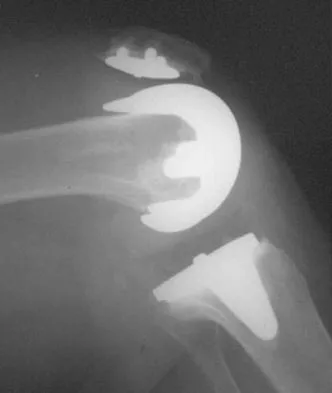

A 40-year-old woman who is an avid tennis player reports the insidious onset of progressive left shoulder pain for the past 2 months. Examination reveals full range of motion with a positive impingement sign. Strength in the supraspinatus and infraspinatus muscles is normal, although stress testing is painful. An earlier subacromial cortisone injection provided good, but only temporary relief. An AP radiograph of the left shoulder is shown in Figure 10. Management should now consist of

Explanation

The radiograph shows calcific deposits within the substance of the supraspinatus tendon. Patients with this condition are prone to recurrent bouts of acute inflammation in the shoulder. While the response to cortisone injection is often dramatic, repeated injections are not recommended because of injury to the collagen fibers. Good results have been obtained with arthroscopic evacuation of the calcium deposits. In one study, the addition of a subacromial decompression did not improve the results. Jerosch J, Strauss JM, Schmiel S: Arthroscopic treatment of calcific tendinitis of the shoulder. J Shoulder Elbow Surg 1998;7:30-37.